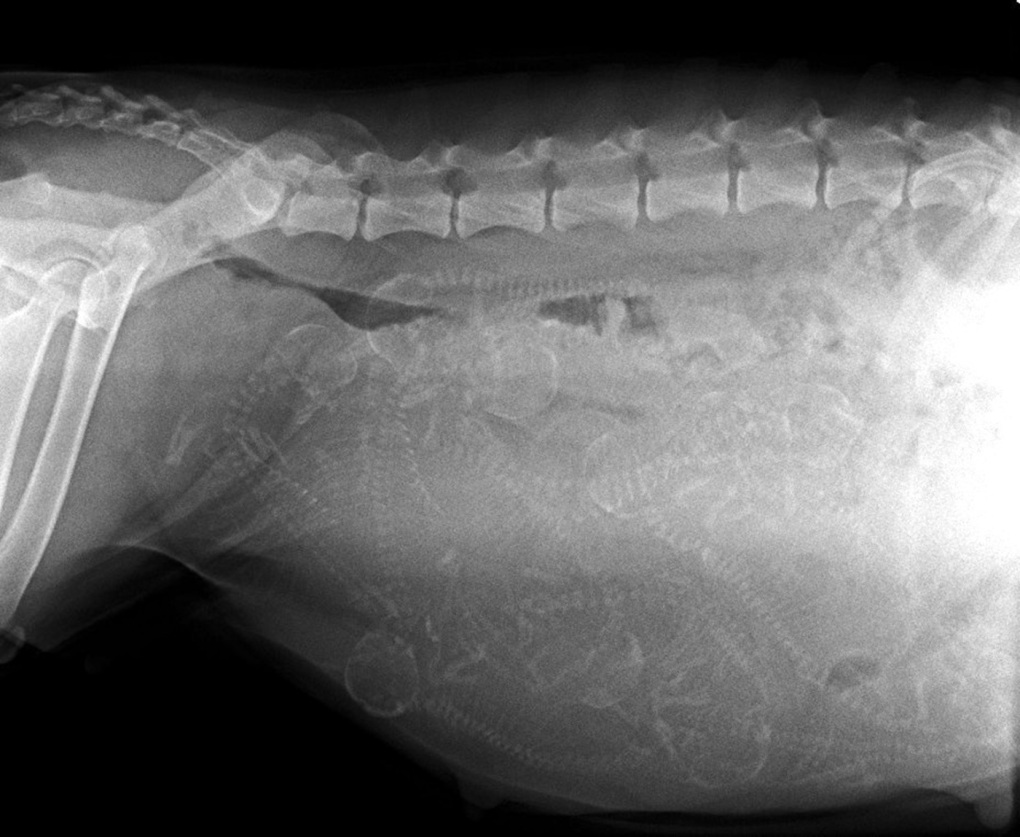

Tag 58

Gestern war ich mit meinem Ftrauchen beim Tierarzt.Jetzt Ich habe stolze 5 kg zugenommen. Anschließend wurde mein Bauch geröntgt und zwischen den vielen Wirbelsäulen wurden 10 Köpfe gezählt. Jetzt heiße es abwarten.